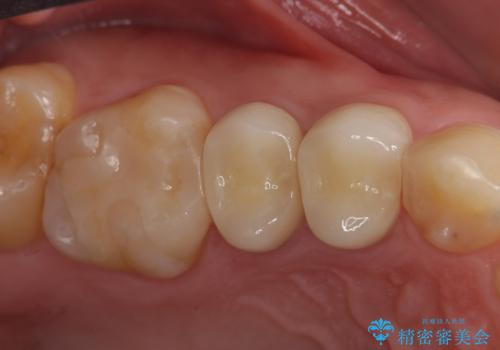

- 右上の銀歯を白くしたいといらっしゃった方の症例です。

右上4、5番目の歯はオールセラミッククラウンによる補綴、6番目の歯はセラミックインレーによる修復を行いました。

今回用いたオールセラミッククラウンは、ジルコニアフレームという白い素材の上にセラミックを盛っているため審美性が非常に高いのが特徴です。

またジルコニアは人工ダイヤモンドの材料にも使われているほど高い強度を持っており、そのためオールセラミッククラウンは審美性だけでなく、奥歯やブリッジの補綴も可能とするクラウンです。